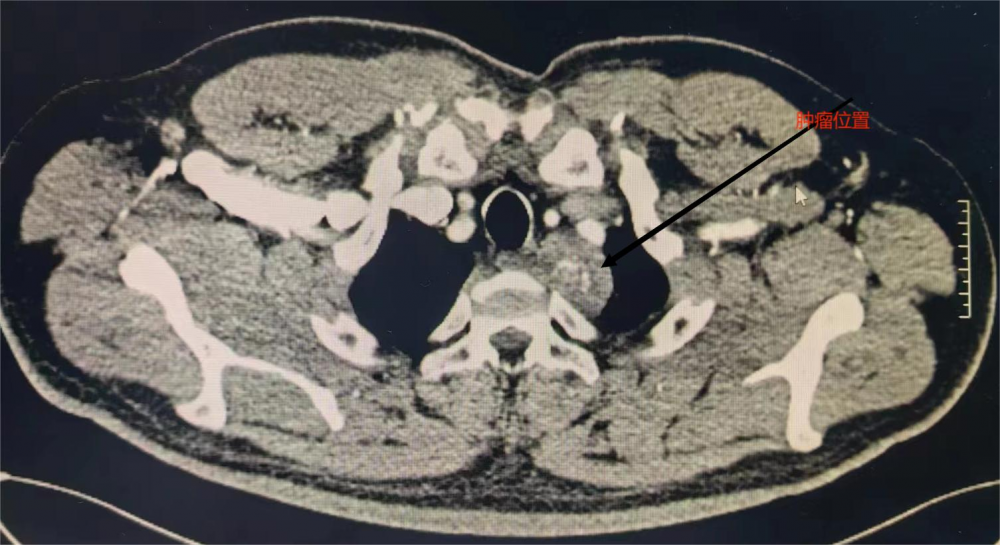

術前CT顯示左前上縱隔腫物

患者,孫×軍,中年男性。 6月22日,查體發(fā)現(xiàn)左前上縱隔胸頂處占位,考慮神經(jīng)源性腫瘤,遂來我院胸外科要求手術治療。胸外科主任季運來看過該患者后,通過認真仔細評估,初步診斷患者為神經(jīng)源性腫瘤。該腫瘤位于胸頂部胸廓入口處,即血管神經(jīng)的出入口處,與無名靜脈、交感神經(jīng)等大血管、神經(jīng)聯(lián)系密切,如不及時做手術、則很快出現(xiàn)腫瘤壓迫血管、神經(jīng)(Horner綜合征)等并發(fā)癥。手術切除病變是其唯一切實有效的治療方法。 與患者及家屬充分溝通后,擬訂為其實施胸腔鏡下腫瘤切除術。手術邀請北京協(xié)和醫(yī)院專家來院指導。6月28日,手術經(jīng)過2個多小時,在全胸腔鏡下成功切除該腫瘤。術后患者恢復順利,未出現(xiàn)Horner綜合征等任何并發(fā)癥,于7月4日康復出院。該手術的順利完成,標志著我院胸外科胸腔鏡技術又上了一個新臺階,真正為胸腔縱膈疾病患者帶來福音。